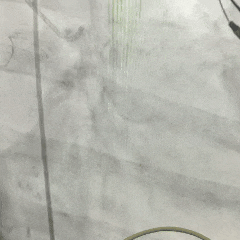

左冠造影检查

20mm球囊扩张,无腰无漏,球囊轻微滑动

TF23瓣膜0位初始释放

瓣膜第一次展开造影评估,位置偏浅,回收调整